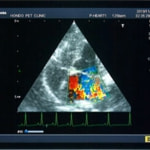

A:超音波カラードップラーでの僧帽弁逆流速度の測定

B:E波とA波の測定

C:僧帽弁逆流の動画(大きく表示させたい場合は、ココをクリックして下さい。)